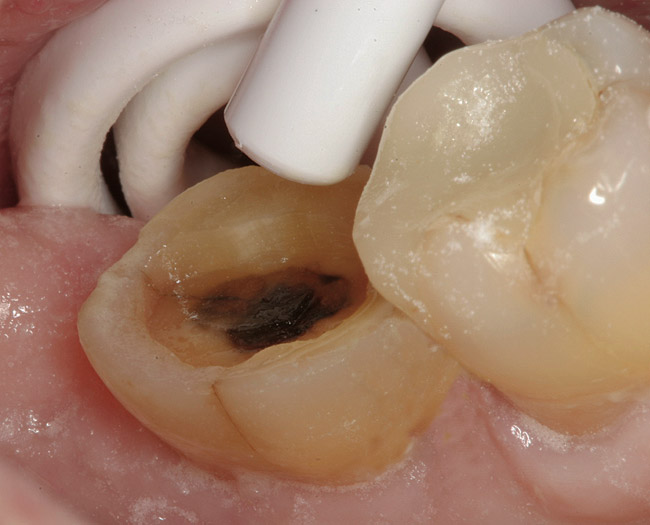

A 70-year-old patient presented with symptoms of a cracked tooth scenario, with intermittent pain upon chewing and thermal sensitivity. The diagnosis was supported through various tests, which determined the lower right second molar had an incomplete fracture that extended from the distal marginal ridge to the mesial marginal ridge. After treatment options were presented, an all-ceramic restoration was decided upon. The tooth was prepared for a nonretentive, adhesively retained all-ceramic restoration ("table top" preparation) (Figure 2 and Figure 3). After the preparation was completed a mild self-etching adhesive was applied to the dentin according to the manufacturer's instruction (Figure 4). There was little concern, if any, of the adhesive reaching the band of exposed enamel. The adhesive was light-polymerized for 5 seconds to secure the layer to the dentin (Figure 5). To eliminate the oxygen-inhibited layer a water-soluble gel was applied to the adhesive and further light-polymerization was completed (Figure 6 and Figure 7). For direct digital scanning cases in which a powdering technique is employed for image capture, it may be more difficult to remove the powder after scanning if the oxygen-inhibited layer is still present.

Figure 3  Facial view (Fig 2) and occlusal view (Fig 3) of nonretentive adhesively retained ("table-top") preparation.

Figure 3

Figure 4  Application of a self-etching adhesive immediately after completion of tooth preparation.

Figure 4